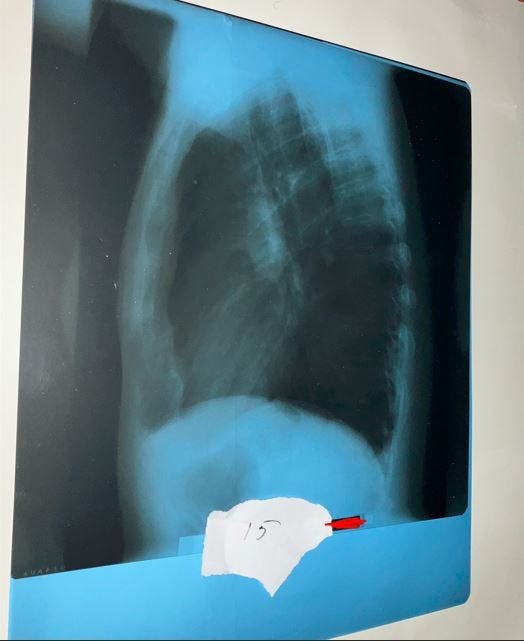

Kuva 15: Sivukuva keuhkoista. Koko 43 x 35 cm.